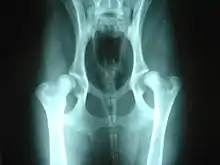

La gravedad de la displasia se puede medir si trazamos el denominado ángulo de Norberg. Éste consiste en trazar sobre una radiografía una línea que vaya desde el centro de una cabeza del fémur, al centro de la otra. Posteriormente, desde ambos extremos se traza otra línea que pase por el borde acetabular dorsal, formando así un ángulo con la anterior. Según la amplitud del ángulo, tenemos que:

- No se presenta displasia si es mayor de 105º.

- Si mide entre 100-105º, el animal tiene displasia leve.

- Si mide entre 90-100º, la displasia es moderada. Se acompaña de enfermedad degenerativa articular y aplanamiento del acetábulo.

- Si mide menos de 90º, la displasia es grave. Puede llegar a presentar luxación.